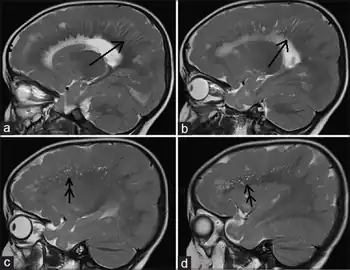

| a, b)MRI shows radial stripes arrow c,d) show scattered dots in form of hyperintensities arrow | |

Different imaging modalities are commonly used for diagnosis. While computed tomography (CT) provides higher spatial resolution imaging of the brain, cerebral cortex malformations are more easily visualized in vivo and classified using magnetic resonance imaging (MRI) which provides higher contrast imaging and better delineation of white and gray matter.[7]

Diffuse pachygyria (a mild form of lissencephaly) can be seen on an MRI as thickened cerebral cortices with few and large gyri and incomplete development of the Sylvian fissures.[3]

Microcephalic osteodysplastic primordial dwarfism (MOPD) type II is an autosomal multisystem disorder including severe pre- and post-natal growth retardation, microcephaly with Seckel syndrome-like facial appearance, and distinctive skeletal alterations. Usually those affected have mild to moderate mental retardation. This female child is the first born of nonconsanguineous parents at 35 weeks gestation through a cesarean section due to intrauterine growth retardation. She had a retarded psychomotor development and was repeatedly hospitalized during her first six months of life due to recurring respiratory infections. Her electroencephalography, auditory brainstem response evaluation, and chromosomal analysis were relatively normal. A brain MRI revealed thickened cerebral cortices with few and large gyri prominently in the frontal and posterior temporal regions, incomplete development of the Sylvian fissures, and dilatation of the posterior horns of the lateral ventricles (colpocephaly). Usually only mild brain malformations are associated with MOPD type II. The imaging findings of this child’s brain most likely represent diffuse pachygyria, a mild form of lissencephaly. This child’s neurodevelopmental findings were mild when compared to previous reports of a well-defined chromosome 17-linked and X-linked lissencephaly in a bedridden patient with severe developmental delays.[8]